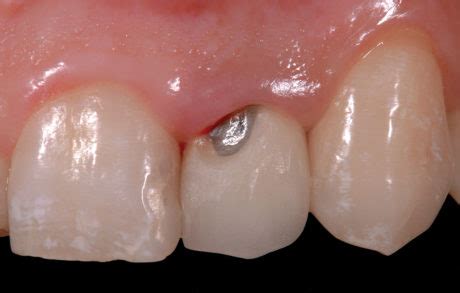

Le scheggiature sono particolarmente frequenti nell'area cervicale delle protesi fisse. Una delle cause principali è la preparazione insufficiente del dente naturale sottostante, che può risultare in uno strato di ceramica più sottile in questa zona. Altre cause di frattura e scheggiatura della ceramica includono:

- Ceramica fratturata con esposizione dell'armatura metallica: Comune nelle protesi in metallo-ceramica.